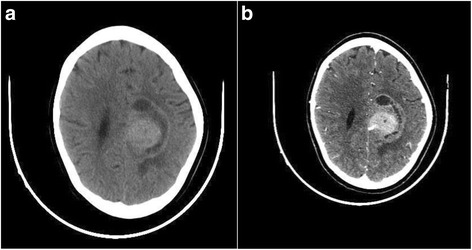

A 10-year-old white girl, presented with a 10-month history of convulsive seizures without signs of intracranial hypertension. A computed tomography (CT) scan revealed a voluminous mass in her perilateral ventricle with similar attenuation to that of cortical gray matter (Fig. 1a), following administration of a contrast product, the mass showed marked enhancement (Fig. 1b). Surgery was performed with complete resection of the tumor. An extemporaneous examination was in favor of a benign ganglioglioma tumor. After fixation in 10 % neutral-buffered formalin, embedding in paraffin and staining with hematoxylin, eosin and safran, histologically the tumor was found to be composed of fibrillated spindle cells and globular large cells, with abundant eosinophilic cytoplasm, and voluminous, eccentric nucleus, and large nucleoli, producing an aspect of ganglion cells; mitosis, necrosis, and microvascular proliferation were not rated (Figs. 2a and 2b). Calcifications and perivascular lymphocytes were observed. In immunohistochemical studies, the spindle cells were positive for glial fibrillary acidic protein (GFAP) (Fig. 2c) and S-100 protein (Fig. 3a). Neurofilament and synaptophysin were negative in either the spindle cells or the large cells (Fig. 3b), and KI67 was not detectable (Fig 3c). An examination that included a dermatological evaluation, a retinal examination, and body imaging revealed no stigmata of tuberous sclerosis. The postoperative course was straightforward.

Fig. 1.

Computed tomography scan revealing a voluminous mass in the perilateral ventricle with similar attenuation to that of cortical gray matter (a), following administration of a contrast product, the mass showed marked enhancement (b)